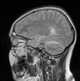

Subdural empyema

An empyema () is a collection or gathering of pus within a naturally existing anatomical cavity. For example, pleural empyema is empyema of the pleural cavity. [Source: Wikipedia ]